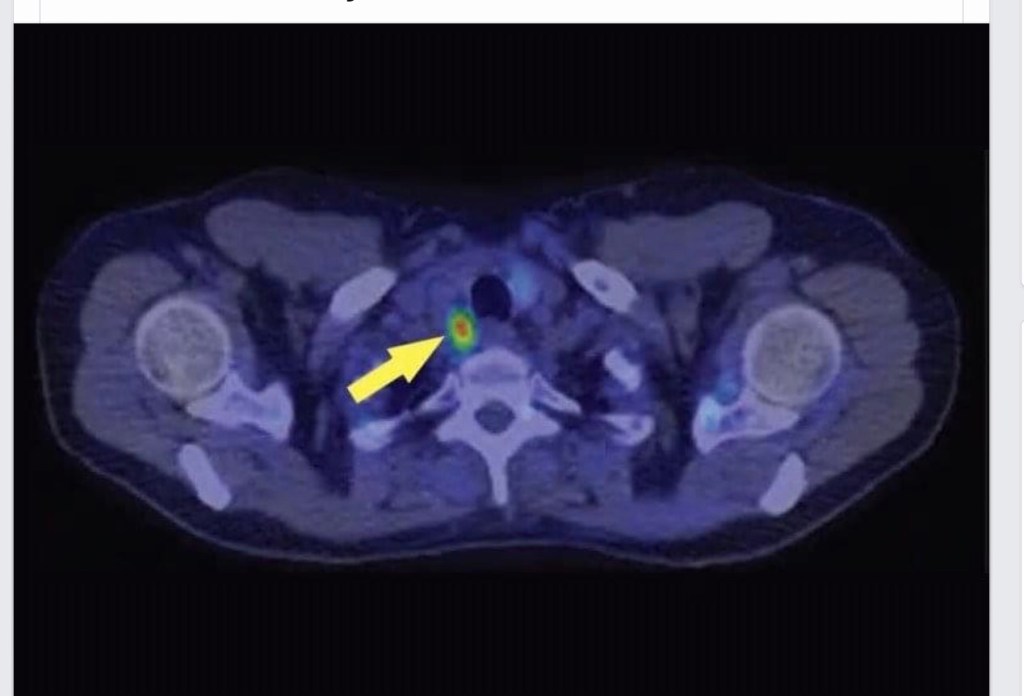

👉In patients with failure to localize on traditional imaging studies, PET choline may be an option and is offered at select centers around the country.